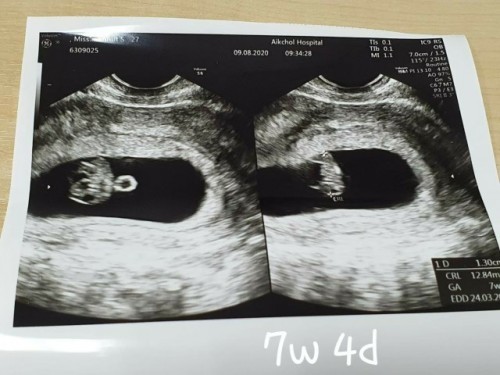

7 Week 4 days เป็นตัวแล้วค่ะ